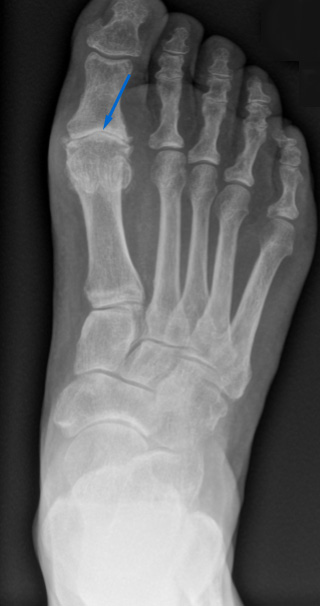

Ein Röntgenbild kann die Diagnose schliesslich sichern. Darauf ist sichtbar, dass der Gelenkspalt verschmälert ist, da sich der Knorpel abgenutzt hat. Zudem lassen sich die typischen Osteophyten und Überlastungen am gelenkangrenzenden Knochen in Form von Skleroselinien (Knochenverhärtung) und Zysten identifizieren.